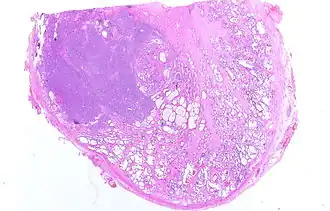

Разрез простаты, поражённой аденокарциномой (слева). Сканер Epson Perfection 1670. Образец окрашен гематоксилин-эозином.